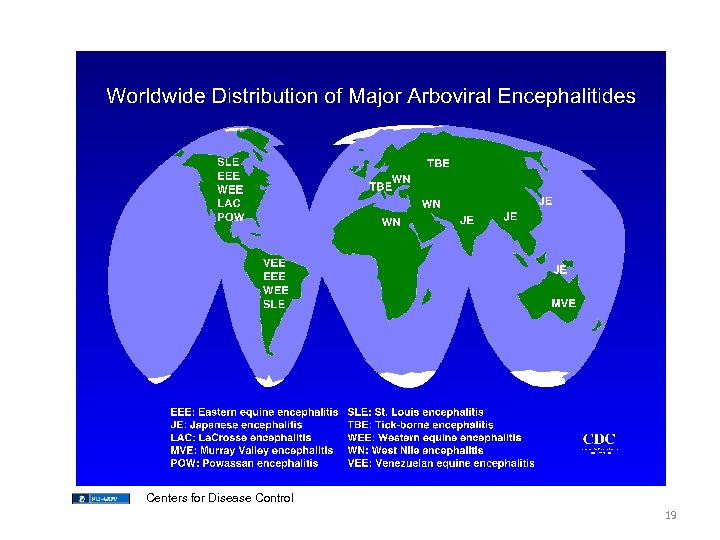

Centers for Disease Control 19